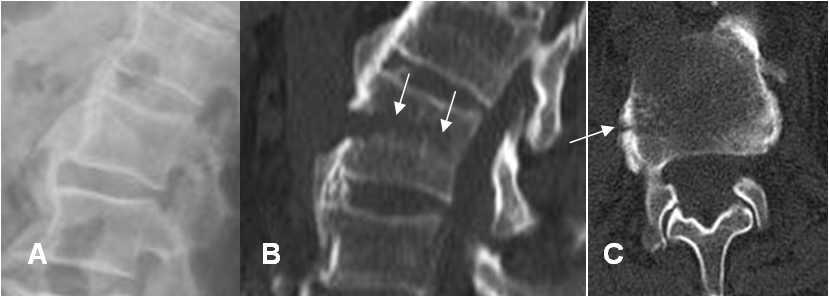

En Rx simple se produce el signo del cuerpo vacío, por el desplazamiento de la apófisis transversa y en el TAC el signo de la faceta vacía, por el desplazamiento de los elementos posteriores y la desaparición progresiva de los pedículos. (46). (Fig 207 A y B).

Fig 207 A. Fractura de Chance.

A: Rx lateral. No se identifican alteraciones.

B: TAC reconstrucción lateral y C: TAC axial. Fractura en sentido transverso, que compromete el cuerpo de L1. No existe fragmento retropulsado.

Fig 207 B. Fractura de Chance.

A: RM sagital en T1, B: RM sagital en T2 y C: RM sagital en STIR.. Igual paciente anterior. Fractura en sentido transverso, que compromete el cuerpo de L1. No existe fragmento retropulsado, ni compromiso del complejo ligamentario posterior.